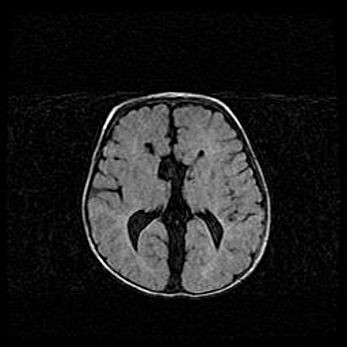

Множественные кисты обоих полушарий головного мозга, наибольшая из них в правой затылочной области. Ассиметричная атрофическая гидроцефалия.

Возраст: 7 месяцев

Вес: 5660 г

Пол: мужской

Окружность головы: 41,5 см

Срок гестации: 28-29 недель

Кисты головного мозга развиваются в результате многоочаговых некрозов вещества мозга и возникают вследствие перенесенной перинатальной инфекции, менингитов, энцефалитов, асфиксии, родовой травмы, расстройств мозгового кровообращения различного генеза. Образованию кист в веществе головного мозга плодов и новорожденных способствуют такие факторы, как высокое содержание в нем воды, недостаточная (или отсутствие) миелинизация и слабая астроглиальная реакция на повреждение.

Кисты могут сочетаться с гидроцефалией и другими поражениями головного мозга.